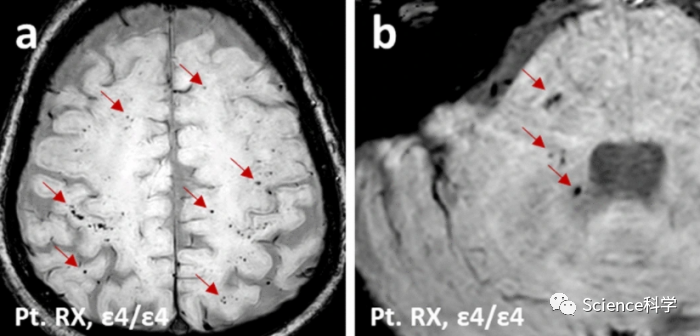

赫尔辛基大学和赫尔辛基大学医院进行的一项研究表明,APOE4等位基因也可能增加与COVID-19有关的脑微出血,并与长病程COVID有关的精神疲劳相关。

该研究称,大约三分之一的芬兰人携带APOE4等位基因,这种基因变体使携带者容易患阿尔茨海默病。在全球范围内,研究人员已经报告了一些观察结果,显示APOE4和COVID-19之间存在联系,包括对SARS-CoV-2感染的易感性和COVID-19死亡率的增加。现在,赫尔辛基大学和赫尔辛基大学医院(HUS)的一个研究小组调查了芬兰人口中APOE4等位基因与COVID-19严重程度之间的联系。

该多学科小组还调查了COVID-19死亡病例的微观脑部变化,以及APOE4与发病六个月后出现的精神疲劳症状之间的联系。

根据研究结果,APOE4等位基因携带者患COVID-19重症的风险增加了一倍以上。此外,在研究中,与其他携带者相比,该等位基因携带者在因COVID-19重症住院后,在其在大脑中发现了更多微出血。